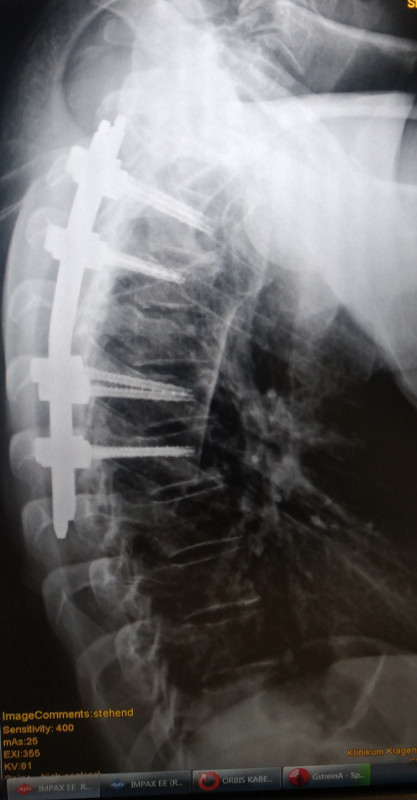

Es waren 2 Halswirbel gebrochen,

3 Brustewirbel und Brustbein..

Brustwirbel wurden eben weil das Brustbein gespalten war on t3-t7 verschraubt.. Kommt ach einem Jahr wieder raus.. Wirklich schlau is es warscheinlich nicht so zu fahren.. Ich weiss

Hals waren Bogenbrüche und Brustwirbel Stauchbrüche